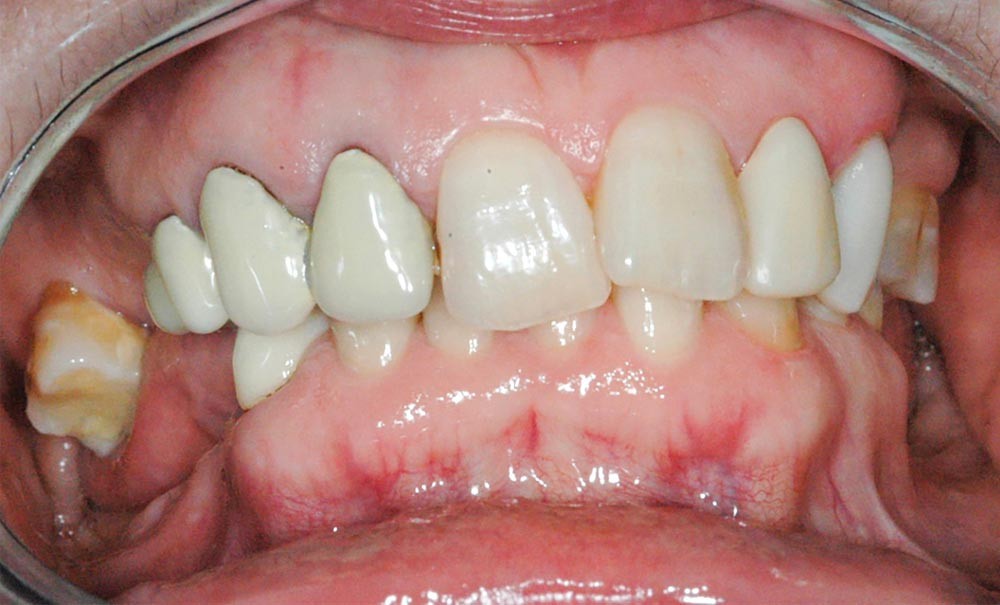

Cet article, rédigé par deux intervenants du congrès et son président, présente un cas clinique dont l’objectif est d’illustrer les étapes diagnostiques et thérapeutiques à mettre en œuvre lors d’une reconstruction occluso-prothétique dans une position thérapeutique corrigeant la relation intermaxillaire initiale.

Les chirurgiens-dentistes sont parfois confrontés à des réhabilitations orales complexes. Les difficultés peuvent être dues à des délabrements ou des migrations dentaires, des affrontements occlusaux chaotiques, mais également à une relation dento-squelettique défavorable. Cela s’accompagne souvent d’une usure excessive des dents, plus ou moins associée à une perte de dimension verticale.

Les praticiens se rendent compte que ces usures se sont développées sur de nombreuses années en modifiant également les relations intermaxillaires. Cette modification constitue ainsi une réponse adaptative à l’évolution continue des usures/délabrements des dents.

Ces situations nécessitent souvent une reconstruction de l’architecture occlusale, avec parfois une modification de la relation intermaxillaire et non pas une restauration prothétique dans le contexte existant.